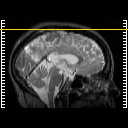

SPECT TC Study #2 -- Slice #49

[Home][Help][Clinical][Tour 1][Tour 2][Tour 3] Slice 49

Click on sagittal image to select slice. Click on thin tickmark to change timepoint, or thick tickmark for overlay.